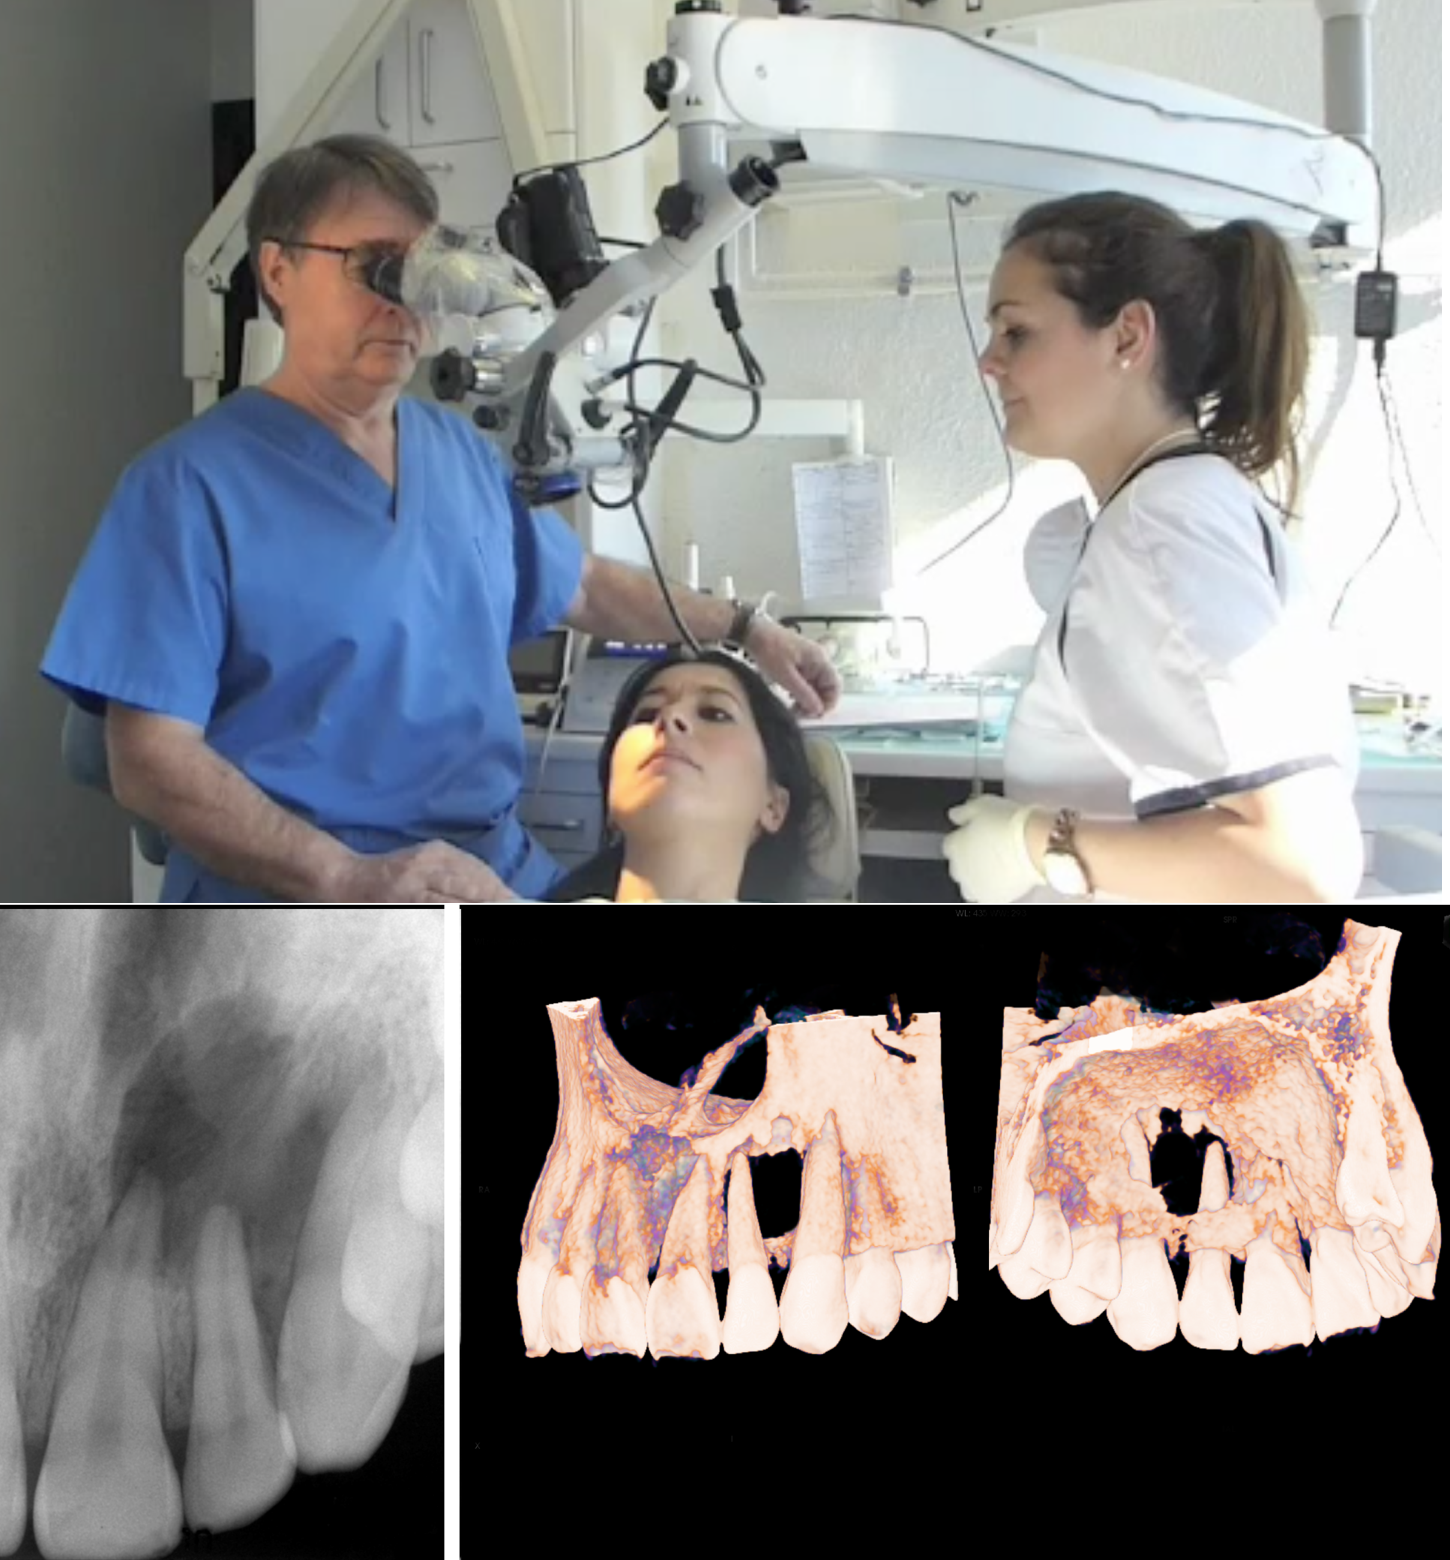

Congreso SECIB en Bilbao (Sociedad Española de Cirugía Bucal) 2015

Congreso SECIB en Bilbao (Sociedad Española de Cirugía Bucal) 2015 Dentists In Espanola Locate and compare dentist in espanola on, yellow pages local listings. We are proud to serve all ages at our oakville practice and are welcoming new patients and their families to our practice. Family dentist espanola centre street dental. Welcome to centre street dental espanola, where your. Locate and compare dentists in espanola mall espanola on, yellow pages local listings.. Dentists In Espanola.